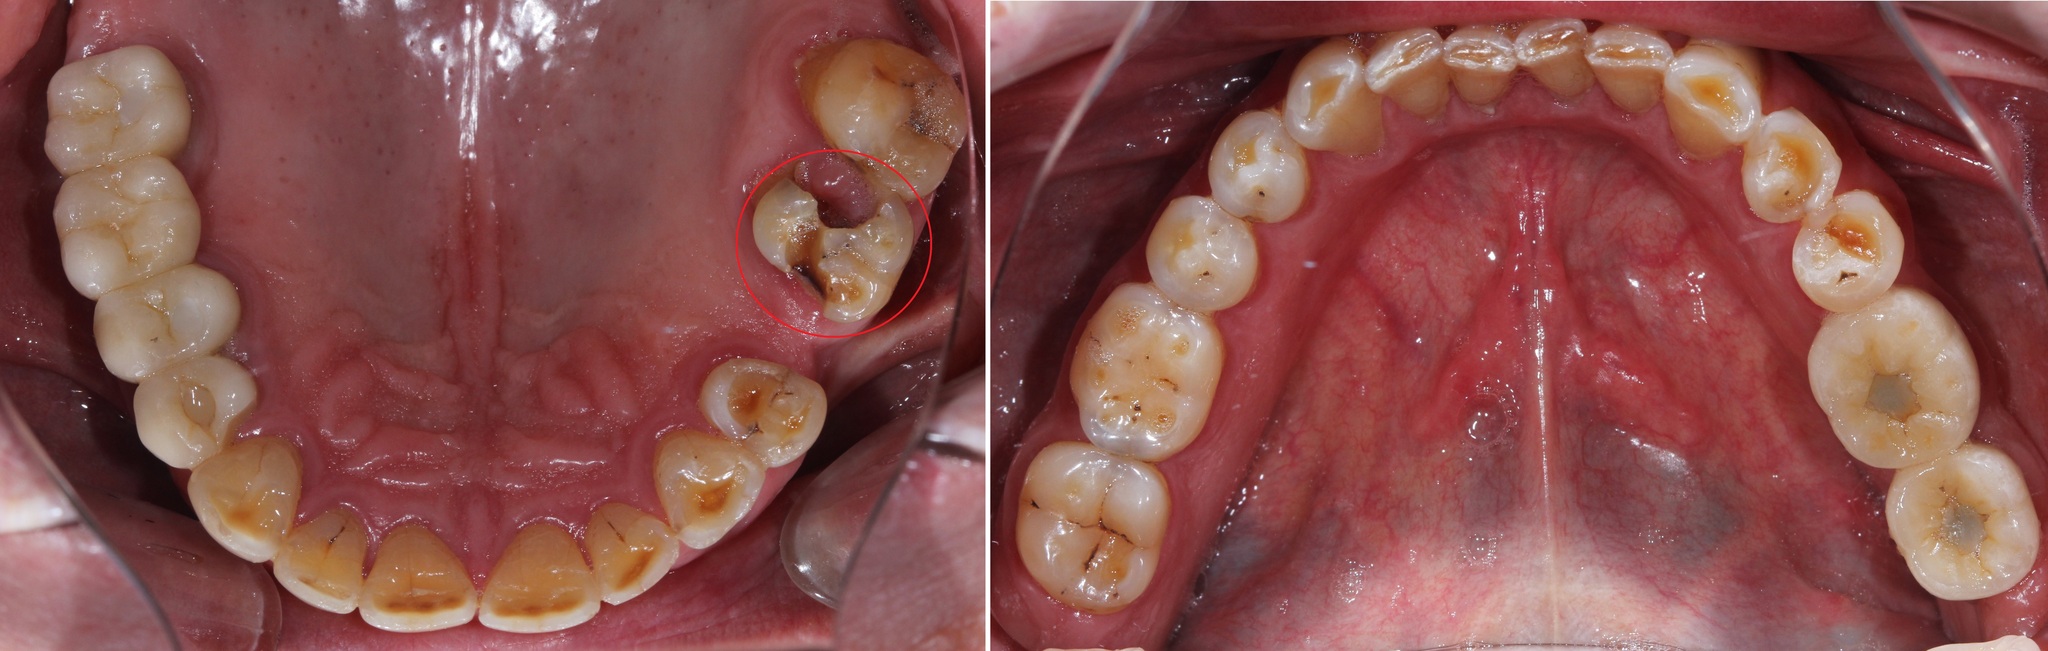

Обратите внимание, как сильно истерты зубы, а в области шеек этих зубов – клиновидные дефекты (некариозное поражение твердых тканей зубов, при которых зуб приобретает форму клина).

Основной причиной появления клиновидных дефектов является перегрузка из-за неправильного смыкания зубов.

Зубы за 3.5 года жизнь потрепала. Режущие края истерлись, появилось больше клиновидных дефектов:

Особенно не выдержал натиска времени 6й верхний левый зуб:

Бедолагу изъело кариесом:

В том числе кариес появился и на контактной поверхности 7о зуба. Маленькая черная точка.